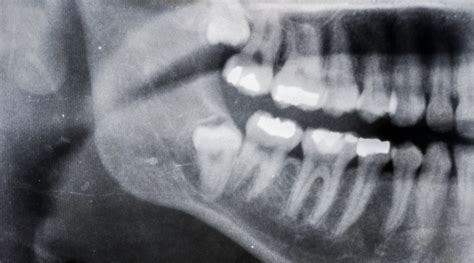

¿Qué puede hacer el dentista en estos casos? Muchas cosas: examinar clínicamente si hay dientes flojos, tomar una radiografía panorámica para ver las posiciones de los dientes permanentes y confirmar que todos estén formándose bien. Con esa información, podrá descartar problemas como agenesias, dientes bloqueados o cualquier anomalía. Si todo se ve normal, te dará tranquilidad para seguir esperando.

Sea temprano o tardío el recambio, unos dientes de leche sanos facilitarán una transición sin complicaciones. Sigue con los buenos hábitos de higiene (cepillado, poca azúcar) y visitas regulares al dentista. Consulta al odontopediatra ante dudas: Si ves alguna de las señales de alerta o simplemente tu instinto de padre/madre te pide asegurarte, pide cita con un especialista en odontopediatría. Una revisión y quizás una radiografía despejarán incógnitas.